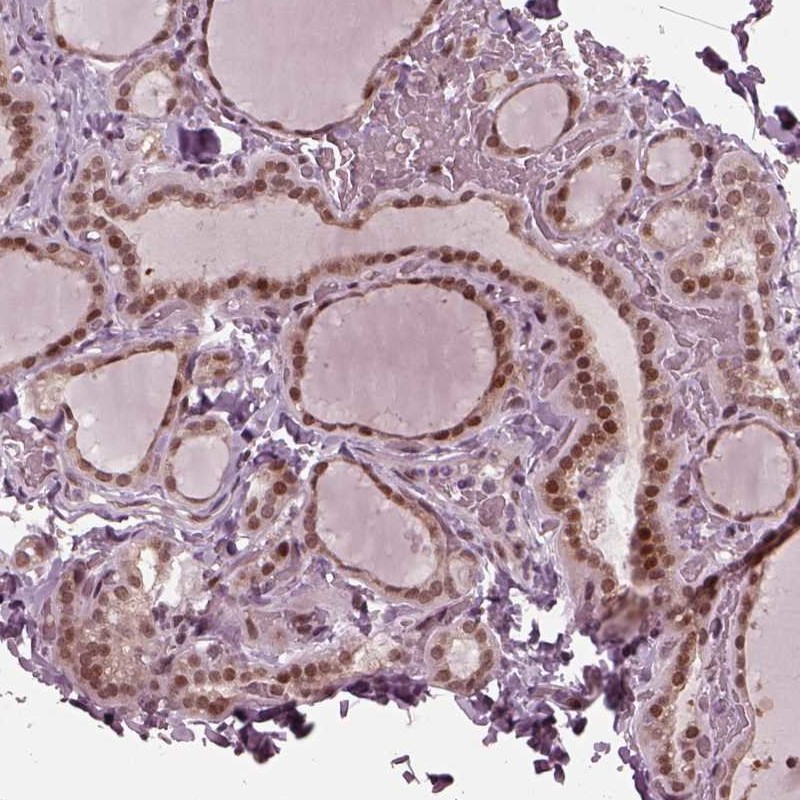

Immunohistochemical staining of human thyroid gland shows strong nuclear positivity in glandular cells.